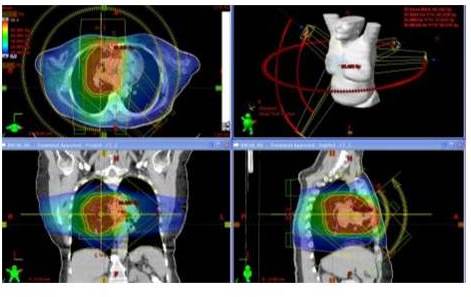

PULMÓN

Para el caso de lesiones torácicas, dependiendo de la ubicación de la lesión, se puede decidir tratamientos con técnica híbrida (cuando la lesión está posteriorizada) o usar RAVM con arcos axiales y sagitales (cuando la lesión está anteriorizada). Esta técnica híbrida consiste en emplear RAVM (con arcos axiales) en conjunto con campos AP-PA de RTC3D gracias a que se necesitan las ventajas de ambas técnicas. RAVM ayuda a disminuir la dosis en corazón y médula espinal pero no ayuda a disminuir la dosis en pulmones. RTC3D con campos AP-PA ayuda a disminuir la dosis en el volumen pulmonar sano pero en la mayoría de los casos aumenta la dosis en médula espinal. Haciendo una ponderación de la dosis para ambos técnicas se llega a poder administrar dosis como 60 Gy sin sobrepasar las tolerancias de las estructuras a riesgo. Para el caso de lesiones anteriorizadas se usa RAVM con arcos axiales y sagitales porque estos arcos sagitales hacen la misma función de los campos AP-PA ayudando a disminuir dosis en los volúmenes pulmonares sanos. Los ángulos de inicio y finalización de los arcos dependen de la ubicación de la lesión. En caso de que la lesión sea medial se usan 2 arcos con punto de inicio y finalización de 150° y 210°, en caso de que esté lateralizada se usan se usan 2 arcos axiales parciales de menor amplitud para así disminuir la dosis en estructuras que no son parte del PTV. En caso de que se usen arcos sagitales la amplitud de estos es simulada previa al tratamiento y la planificación en la sala de tratamiento para garantizar que no exista riesgo de colisión del cabezal con el paciente. Se emplean Rayos X de 6 MV. Al igual que los tratamientos de cabeza y cuello existe una gran ventaja de la RAVM sobre la RTIM porque con la primera los tiempos de tratamientos son alrededor de 5 min a diferencia de con RTIM los cuales oscilan alrededor de 20 min.

En la siguiente Figura se observa la distribución de dosis en plano axial, coronal y sagital del plan para el tratamiento para un cáncer de células no pequeñas de pulmón usando arcos axiales y campos de RTC3D.

En la Figura 11 se muestra la distribución de dosis en planos axial, coronal y sagital para el plan de tratamiento de una lesión pulmonar usando arcos axiales y sagitales de RAVM.